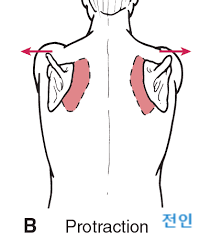

후만과 거북목으로 인해 견갑골이 앞으로 빠지는 전인상태(Scapular protraction)이 되면서 견봉하공간이 좁아지면서 어깨 충돌가능성이 증가할 수 있습니다.

앞서 말했던 원인들에 의해서 겹갑골은 과도한 견갑골의 앞으로 빠진상태인 전인상태(견갑골 벌어짐, Protraction, 후인이 잘 안됨)와 견봉 올림(Acromial elevation)이 어려움에 의해서 충돌이 더욱 쉽게 일아날 수 있습니다.

굽은등, 거북목 -> 견갑골 전인상태 -> 견봉하공간 좁아짐 -> 충돌 증가